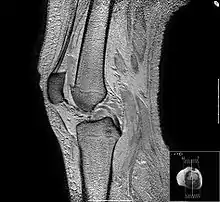

En imagerie médicale, l'IRM est principalement dédiée à l'imagerie du système nerveux central (cerveau et moelle épinière), des muscles, du cœur et des tumeurs. Grâce aux différentes séquences, on peut observer les tissus mous avec des contrastes plus élevés qu'avec la tomodensitométrie ; en revanche, l'IRM ne permet pas l'étude des corticales osseuses (tissus « durs ») trop pauvres en hydrogène, ni donc la recherche fine de fractures où seul l'œdème péri-lésionnel pourra être observé.

- L'antenne genou : il s'agit d'une antenne émettrice-réceptrice ou réceptrice simple. Il s'agit d'une antenne modulaire de 22 cm de diamètre (peut varier). Elle est adaptée à l'exploration du genou, mais aussi du pied et de la cheville.

- les articulations et les structures adjacentes (hanches, genoux, ménisques, ligaments croisés), notamment chez les sportifs ;